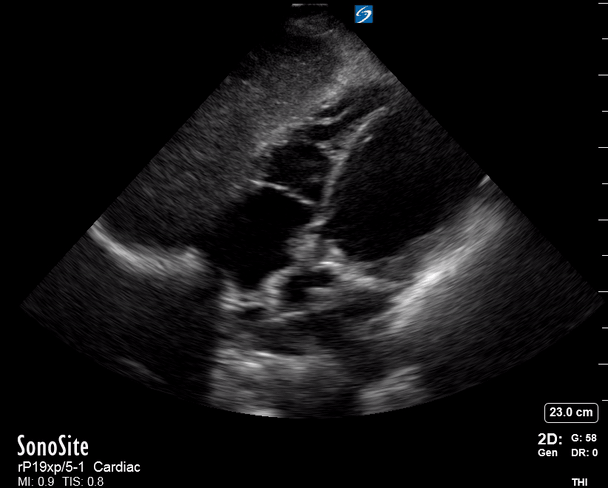

CARDIAC TAMPONADE

Progressively rising pressure translates into evolving tamponade, and this accompanies a series of ultrasound findings:

Initially, the RA collapses during ventricular systole (closed AV valves).

Followed by RV collapse in ventricular diastole (open AV valves).

Ultimately leading to LV collapse.

In addition, the presence of a non-collapsible, plethoric IVC is one of the most sensitive signs of tamponade, and a finding easy to visualise. Conversely, a pericardial effusion in a haemodynamically stable patient with a collapsible IVC is unlikely to represent tamponade.

Chamber collapse can be assessed in M-mode, where the collapsing RV is seen as a notch that takes place right after the mitral valve opening and before its closure (during diastole).

M-mode is used to demonstrate RV collapse (arrow) occurring right after mitral valve opening during diastole. (star = pericardial effusion, 1. RV free wall, 2. Interventricular septum, 3. mitral valve, 4. LV free wall). From: The "5Es" of emergency physician-performed focused cardiac ultrasound (11).